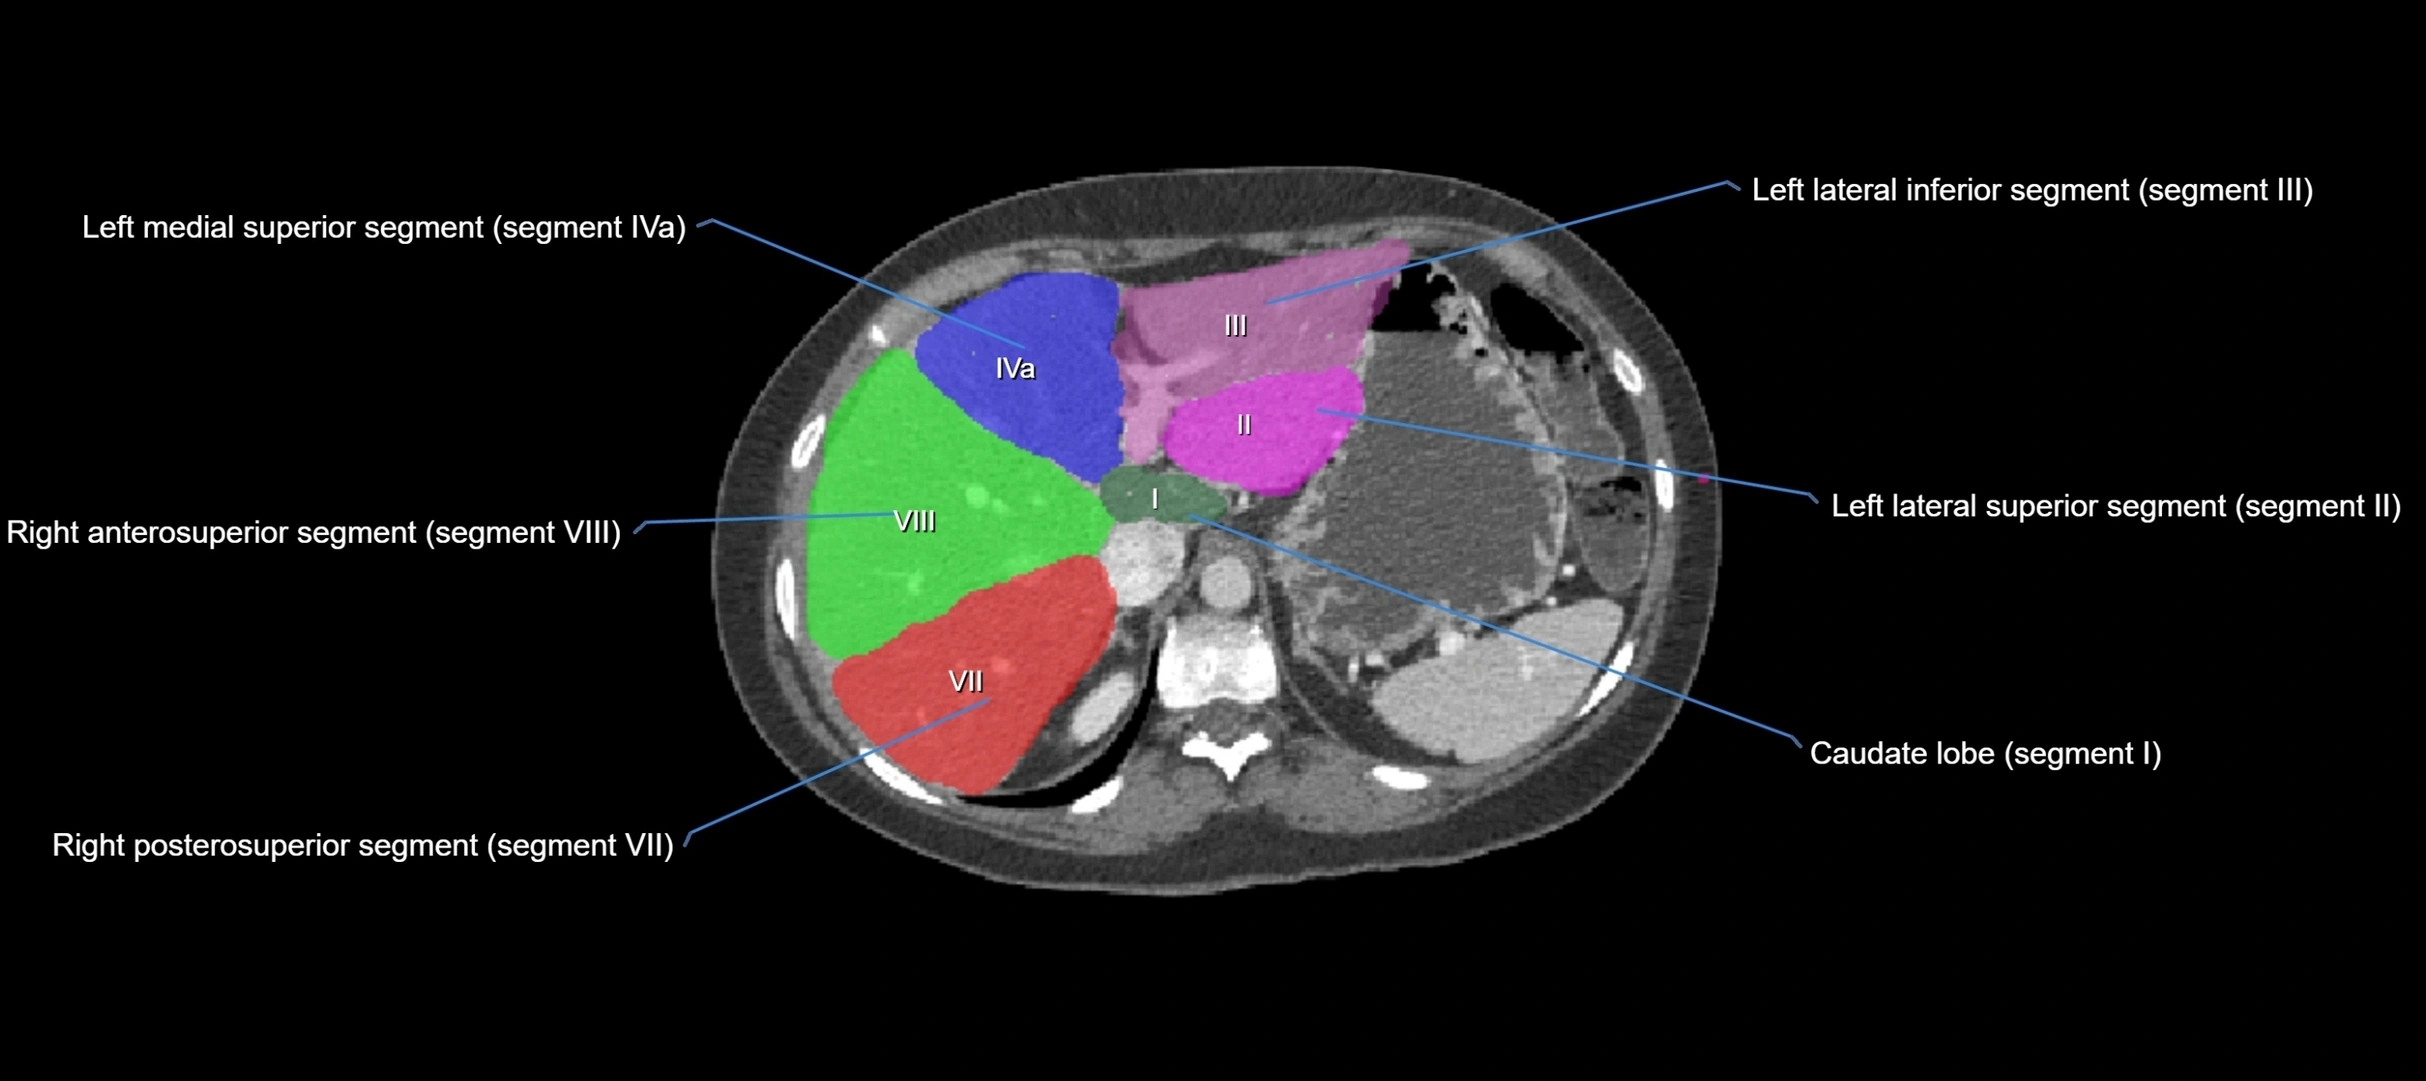

The caudate lobe of the liver is a distinct anatomical subdivision of the liver, designated as segment I in Couinaud’s classification. It lies on the posterior surface of the liver, between the fissure for the ligamentum venosum (left boundary) and the groove for the inferior vena cava (IVC) (right boundary). Superiorly, it is related to the posterior liver surface, and inferiorly it is separated from the left lobe by the porta hepatis.

CT Image

image